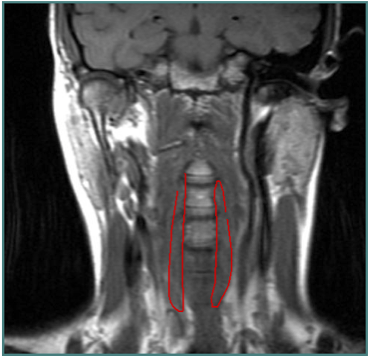

ANTEROCOLLIS

- Scalenus medius and anterior

- Longus Colli

Insert Spine

ANTEROCAPUT

MOTION IN SAGITTAL PLANE- ANTERO

FLEXION

Anterior muscles acting together